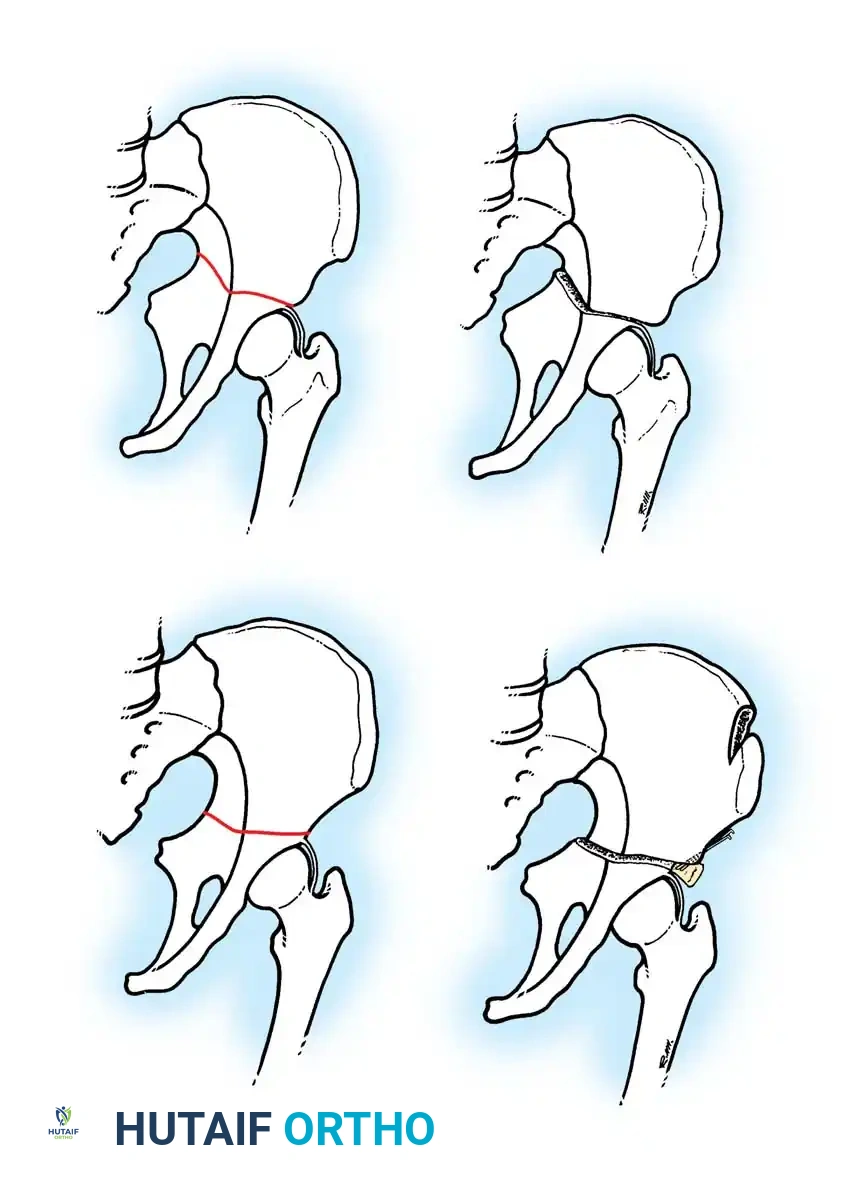

Surgical Management: Pelvic Osteotomies

Innominate osteotomies, such as the Salter osteotomy, provide containment by redirecting the acetabulum to cover the anterolateral aspect of the femoral head without altering the proximal femoral anatomy. This is particularly advantageous in older children where remodeling of a varus femur is less predictable, or in cases where limb shortening is undesirable.

Salter Innominate Osteotomy Technique:

1. Approach: A Smith-Petersen (anterior) approach is utilized. The interval between the tensor fasciae latae and the sartorius is developed.

2. Exposure: The iliac apophysis is split, and the inner and outer tables of the ilium are stripped subperiosteally down to the greater sciatic notch.

3. Osteotomy: A Gigli saw is passed through the sciatic notch and directed anteriorly to exit at the anterior inferior iliac spine (AIIS).

4. Redirection: The distal acetabular fragment is hinged on the pubic symphysis and rotated anterolaterally, pivoting on the triradiate cartilage.

5. Grafting and Fixation: A triangular wedge of bone (harvested from the anterior iliac crest) is impacted into the osteotomy gap. The construct is stabilized with two or three threaded Kirschner wires driven from the proximal ilium, through the graft, and into the distal fragment.

Salvage Procedures for Late Disease

In late-stage LCPD presenting with established hinged abduction, severe coxa magna, and loss of sphericity, traditional containment procedures are contraindicated as they will exacerbate impingement.

Valgus Extension Osteotomy:

For patients with hinged abduction, a proximal femoral valgus osteotomy is the procedure of choice. By placing the femur into valgus, the extruded anterolateral bump is rotated away from the lateral acetabular rim, allowing the medial, more spherical portion of the femoral head to articulate with the acetabulum. This dramatically relieves pain and improves abductor mechanics.